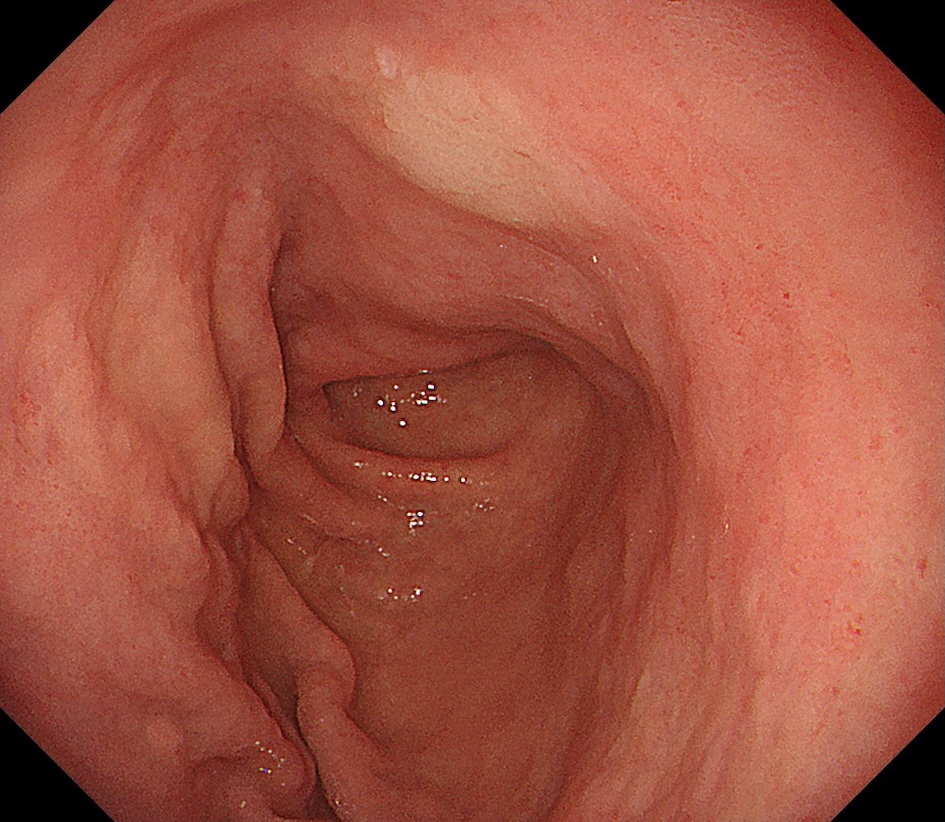

• 白色光観察①(中遠景)

強調設定:B8

図1

白色光観察:体下部小彎に約15mm大の褪色調を呈する平坦な病変を認める。病変辺縁は一部で不明瞭である。